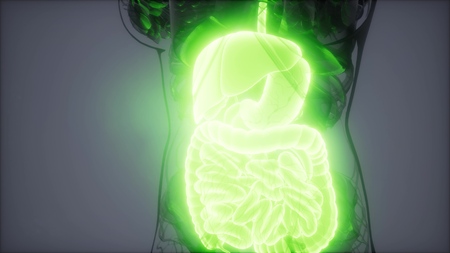

3d rendered medically accurate illustration of male Digestive System

Human Digestive System Anatomy For Medical Concept 3D Illustration

Human Digestive System Anatomy For Medical Concept 3D Illustration